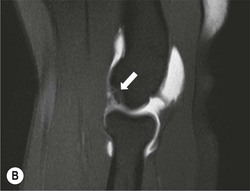

The capitellum is the third most commonly affected site in osteochondritis dissecans (after the knee and ankle). It commonly affects teenagers and young adults. A focal osteochondral fragment or defect may be visualised on radiographs. Cross-sectional imaging with MRI, MR arthrography or CT arthrography is used to detect radiographically occult lesions and for grading osteochondral lesions (Fig. 46-21). The osteochondral fragment may remain in situ or lie remotely within the elbow joint. Fluid SI at the base of the osteochondral lesion on MRI, or contrast medium tracking around the fragment on arthrographic images, is a sign of an unstable lesion. Integrity of the overlying articular cartilage is a good sign of stability.